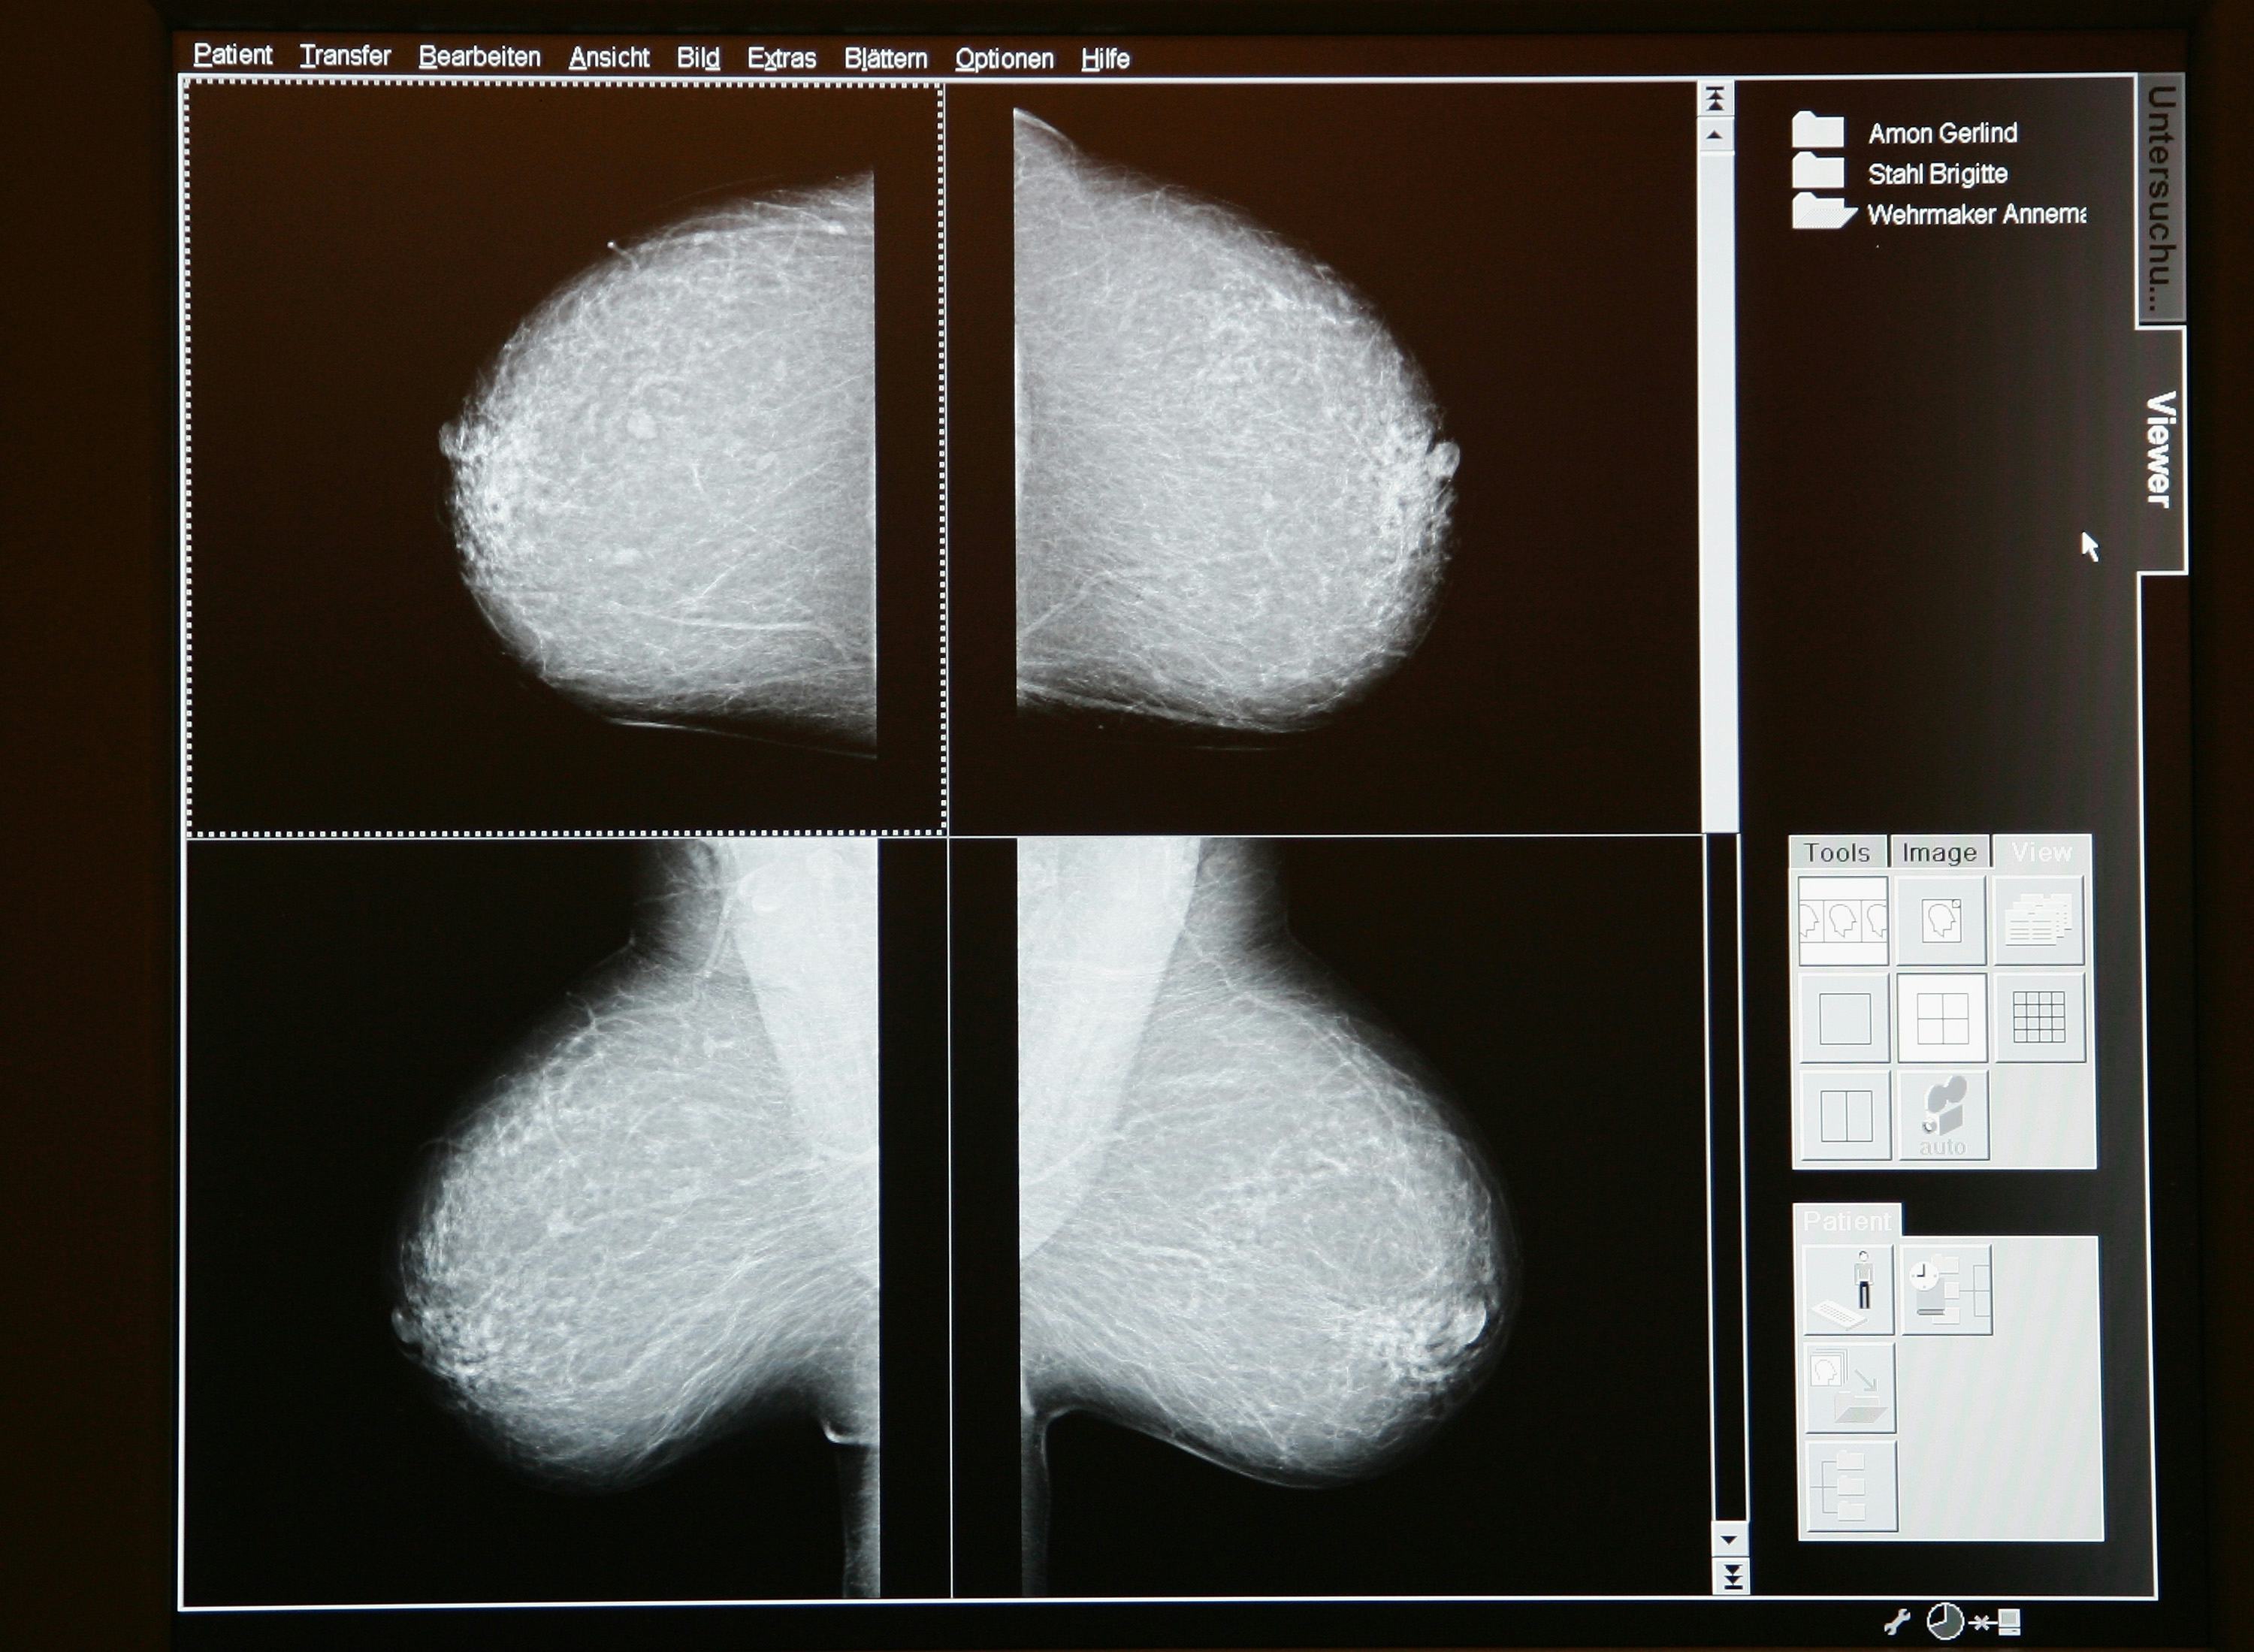

From dxosmeegs.blob.core.windows.net

Mammogram XRay at David Shapiro blog How Often Should You Have A Mammogram In Canada Starting at age 50 and ending at age 74 or 75, asymptomatic individuals at average risk. have a mammogram every 2 years. regular screening mammograms are important because they can monitor changes to the breast over time and find breast. If you are 75 or older. if you are 40 to 74 years old, have a mammogram. How Often Should You Have A Mammogram In Canada.